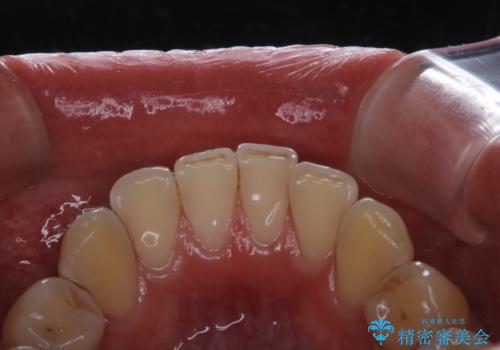

紅茶による着色を1日できれいに

- 紅茶を頻繁に飲むため、歯の黄ばみが気になるとのことでした。PMTC60分コースを行いました。

また、仕上げのトリートメントでは歯の表面の凸凹にミネラルを補給して、ツルツルの表面に仕上げます。定期的にPMTCを行うことにより、歯質の強化になり着色がつきにくい状態になります。

普段の飲食物・歯磨き・生活習慣などにより着色の付き具合には個人差があります。どれくらいの頻度で行うことがベストか、PMTCのコースの時間などはその都度担当の歯科衛生士とご相談します。